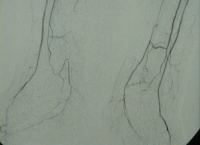

DSA preoperatoria del paciente:

PM 311-5

Abb. 5: Teilverschlüsse der Unterschenkelarterien bds.

PM 311-6

Abb. 6: Verschluss der A. tibialis posterior rechts